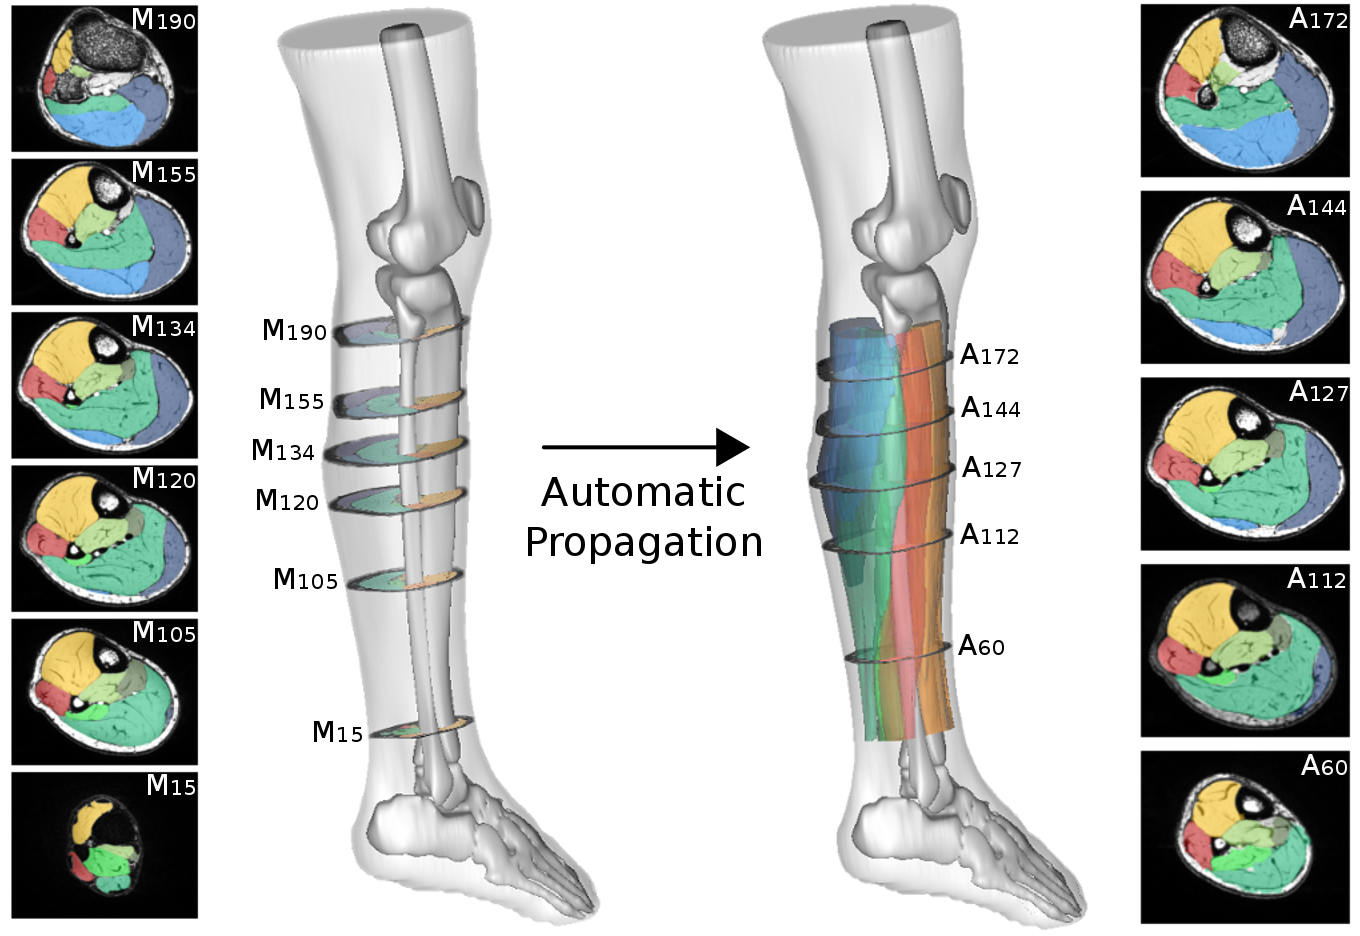

La segmentation manuelle et automatisée des muscles individuels dans les images par résonnance magnétique a été reconnue comme difficile étant donné la discontinuité ou l’absence de limites visibles entre les muscles. Dans ce présent rapport de stage, nous avons proposé un algorithme qui, à partir d’une segmentation réalisée sur une image d’un sujet suite à une première acquisition, propose la segmentation automatique des muscles individuels des images de ce même sujet à d’autres acquisitions. Grâce à des points caractéristiques extraits automatiquement et mis en correspondance entre ces deux images, nous avons pu montrer que le guidage du recalage non-linéaire améliore la propagation de la segmentation, avec un coefficient de similarité Dice supérieur à 0,94.

Semi-automatic segmentation by propagation

Computational anatomy aims to develop computer processing methods to enrich diagnosis by extracting objective and clinically useful information from medical images. The deployment of such methods remains limited for the exploration of soft tissue organs, especially for the study of pelvic floor disorders and neuromuscular diseases via magnetic resonance imaging. In these domains, the segmentation step is essential to allow the characterization of physiological alterations occurring within the organs of interest. The high phenotypic variability in these pathologies has so far limited the development of robust automatic segmentation methods, limiting clinical research on large populations. To overcome this challenge, the main contribution of my thesis was the development of a supervised segmentation approach based on diffeomorphic image registration propagation methods.